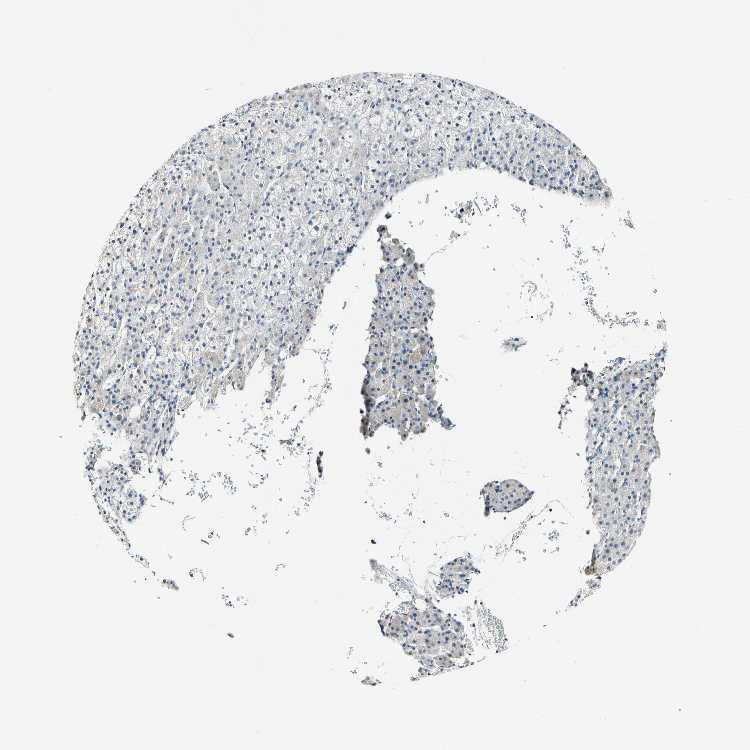

ADRENAL GLAND - Antibody stainingi

Antibody staining in the annotated cell types in the current human tissue is reported as not detected, low, medium, or high, based on conventional immunohistochemistry profiling in selected tissues. This score is based on the combination of the staining intensity and fraction of stained cells.

Each image is clickable and will lead to virtual microscopy that enables deeper exploration of all samples and also displays staining intensity scores, fraction scores and subcellular localization as well as patient and tissue information for each sample.

Antibody HPA010080

Glandular cells Not detected